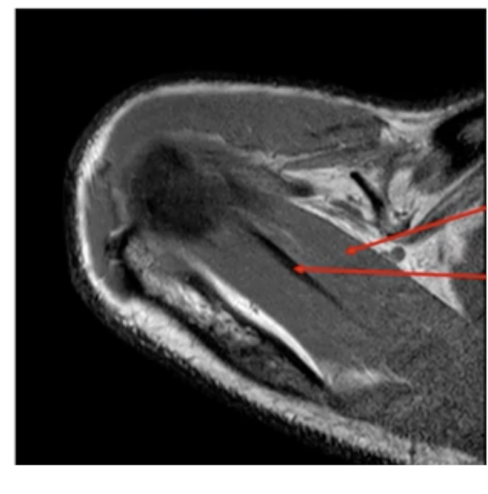

What are the sequences and what is the pathology?

• T1, STIR, T1FS C+

• Tissue lipoma- benign tumour made of fat tissue